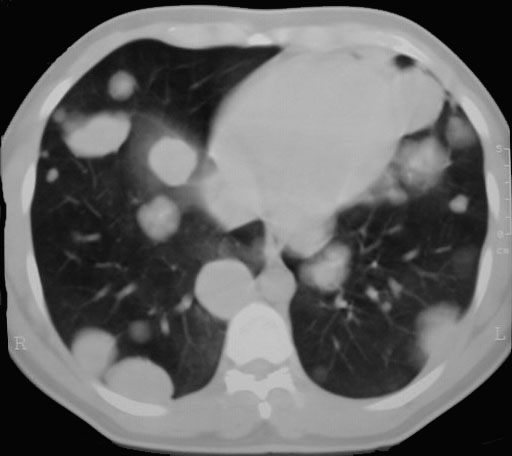

SIGNO DE LA SUELTA DE GLOBOS

La presencia de múltiples nódulos pulmonares bien definidos de distribución bilateral y aleatoria, de diferentes tamaños, es muy sugerente de metástasis pulmonares. El nombre del signo es muy gráfico.

El caso que mostramos corresponde a un paciente con metástasis de seminoma. Abajo, la imagen de TC del mismo paciente.